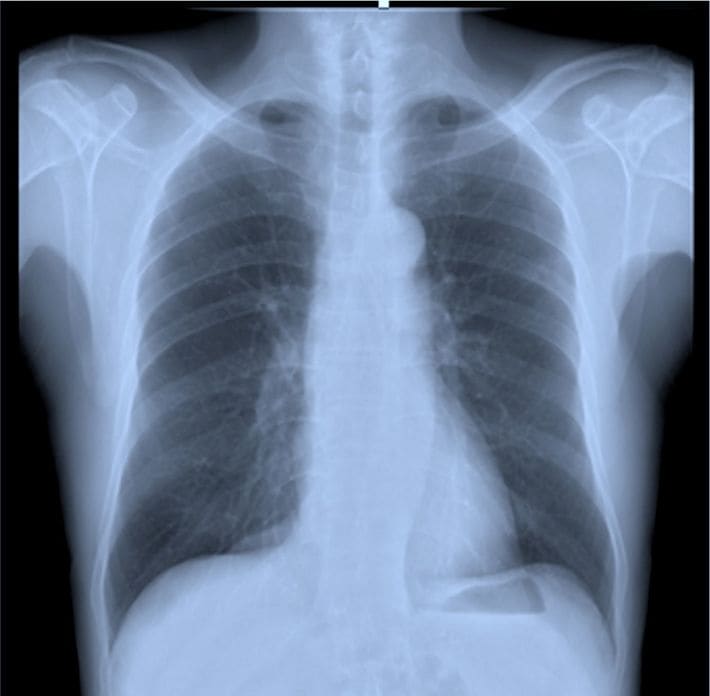

胸部X線の画像